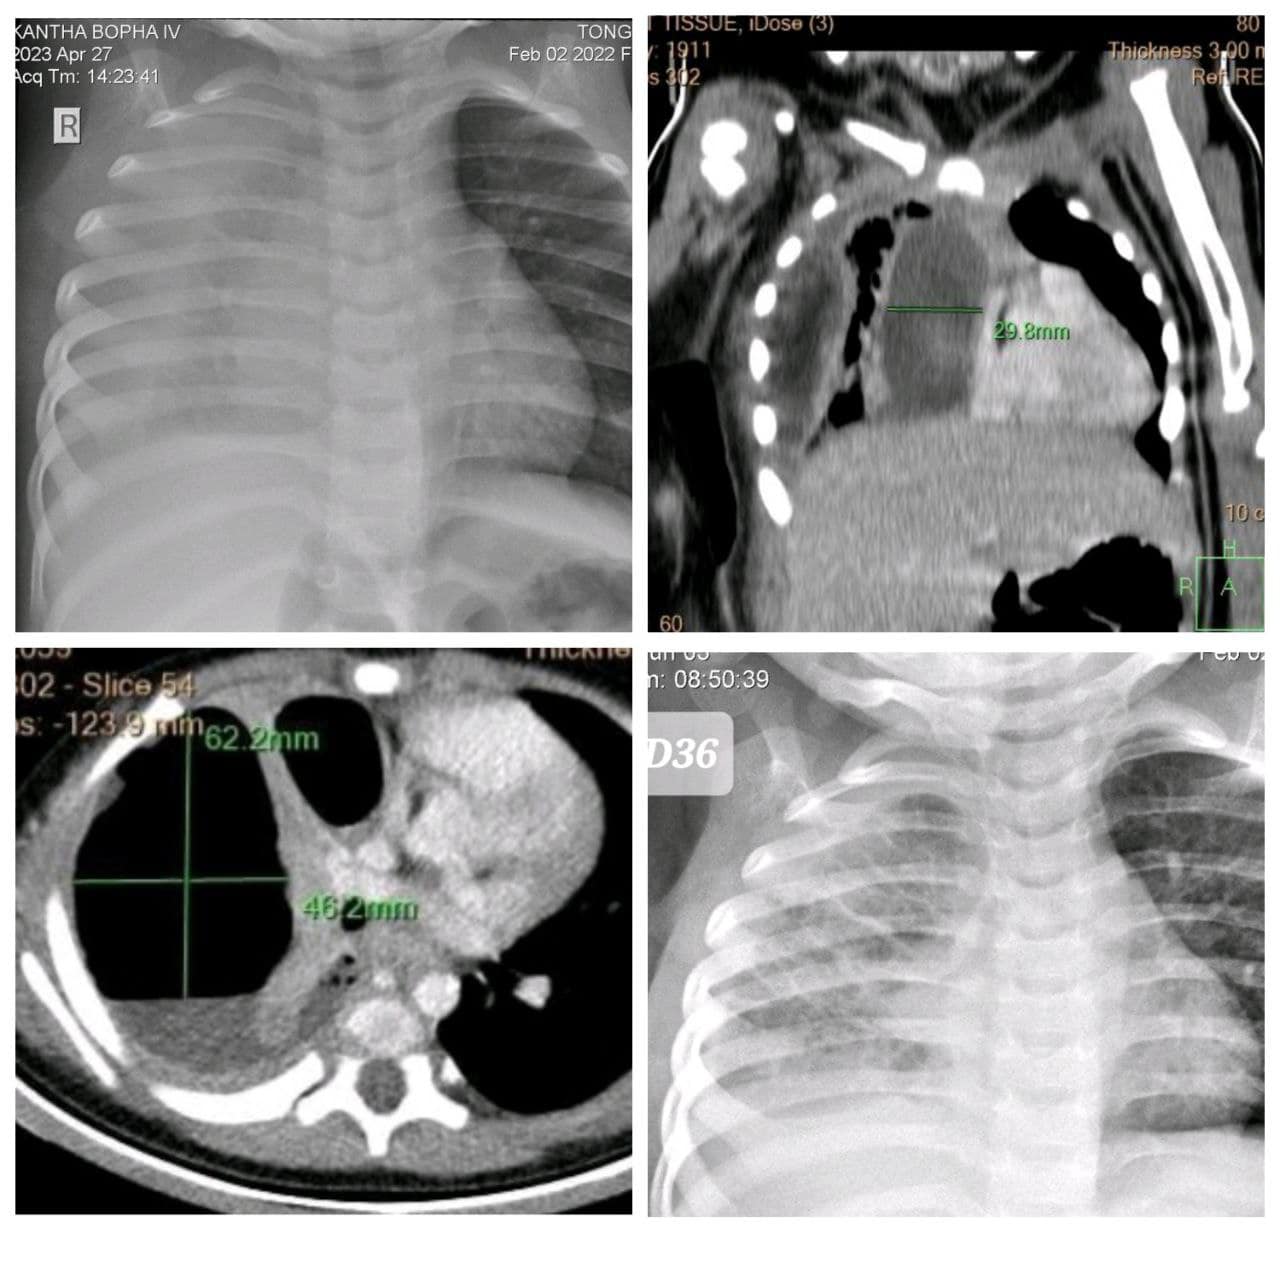

នៅថ្ងៃទី០៨ ខែមិថុនា ឆ្នាំ២០២៣ យោងតាមការចុះផ្សាយរបស់ មន្ទីរពេទ្យគន្ធបុប្ផា បានឱ្យដឹងថា ក្មេងស្រីតូចម្នាក់ មានជំងឺរលាកសួតក្លាយជាបូសសួតខាងស្តាំយ៉ាងធ្ងន់ធ្ងរបំផុត ត្រូវបានមន្ទីរពេទ្យគន្ធបុប្ផាសង្រ្គោះជីវិតទាន់ពេល ។

ក្មេងស្រីតូចម្នាក់នេះ មានអាយុ១ឆ្នាំ មកពីខេត្តកំពង់ចាម មកដល់មន្ទីរពេទ្យគន្ធបុប្ផាដោយដង្ហក់ហត់ថប់ដង្ហើម និងបាត់បង់ស្មារតីធ្ងន់ធ្ងរបំផុត មានជំងឺរលាកសួតក្លាយជាបូសសួតខាងស្តាំយ៉ាងធ្ងន់ធ្ងរបំផុត នាងត្រូវបានជួយសង្រ្គោះជីវិតនៅផ្នែកសង្រ្គោះបន្ទាន់គន្ធបុប្ផាអស់រយៈពេល៣៦ថ្ងៃ។